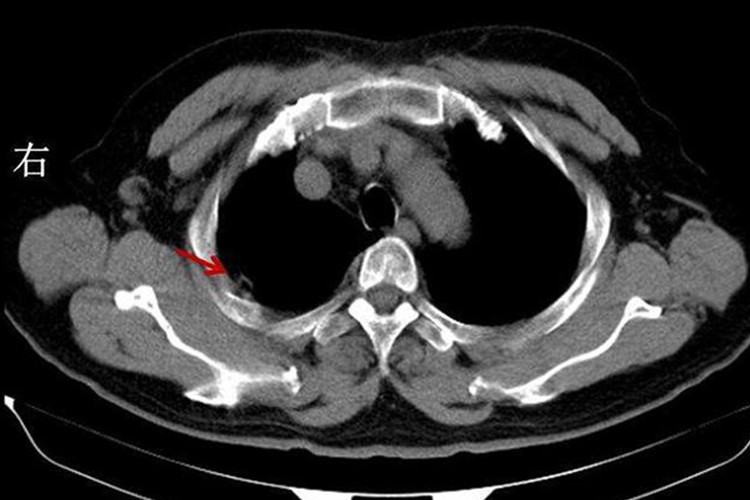

干性胸膜炎:CT表现为与后胸壁胸膜平行的水样密度弧形带状影。